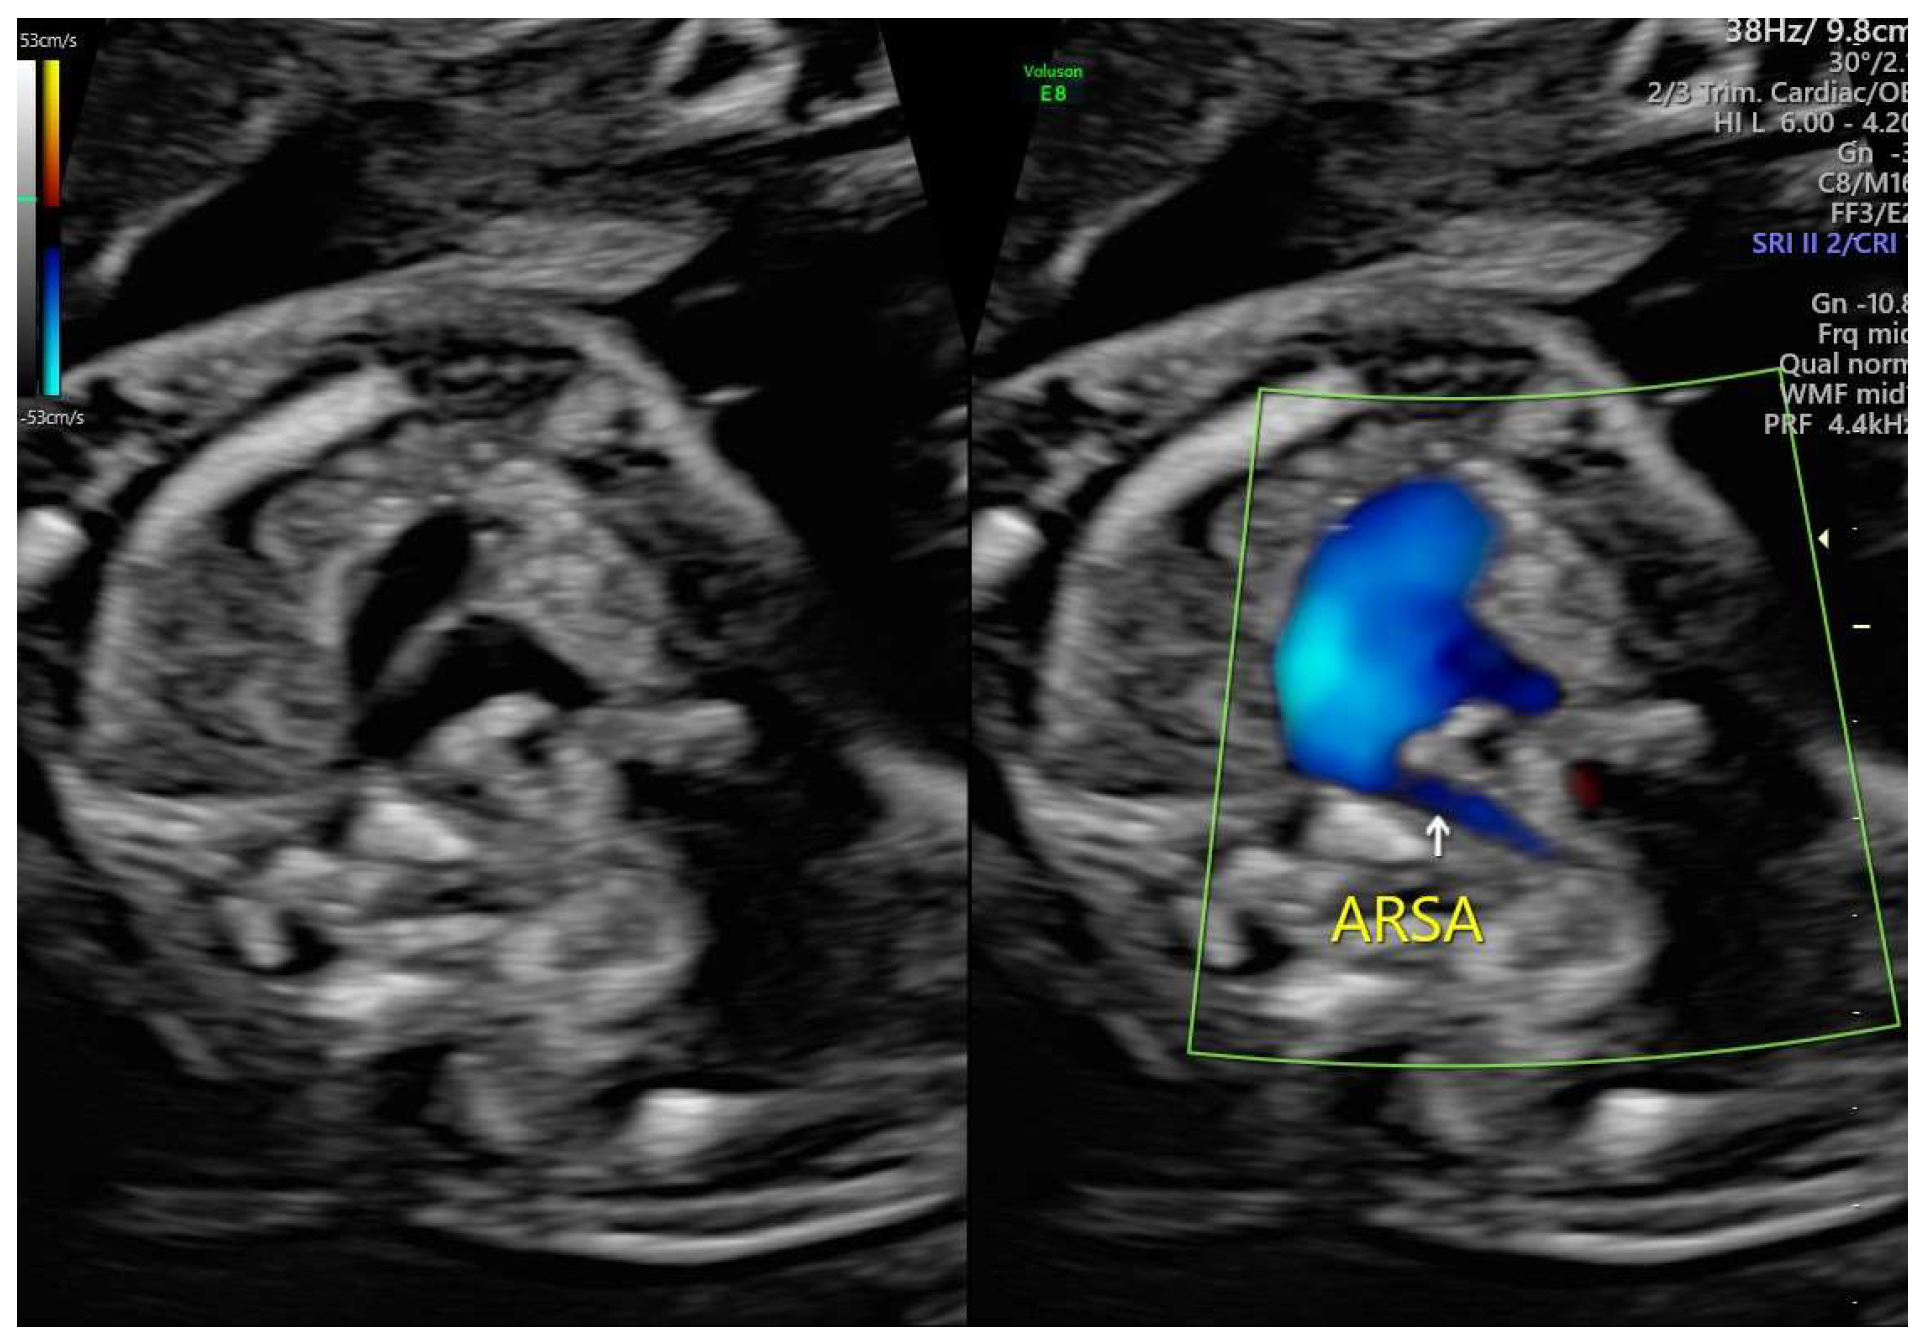

ARSA cases were identified during routine prenatal transabdominal ultrasonography of unselected patients at our hospital between July 2020 and June 2023. Grayscale and color Doppler ultrasonography in the transverse three-vessel view assessed the right subclavian arteries. The presence of ARSA in the transverse plane was meticulously confirmed by two operators with specialized experience using the GE Voluson E8 and S10 ultrasound machines. The examination was performed during the second trimester at a gestational age ranging between 21 and 23 weeks and adhered to the International Society of Ultrasound in Obstetrics and Gynecology guidelines for structures and detection techniques. ARSA incidence in the second trimester ranges from 0.4% to 1.5% in chromosomally normal fetuses [21]. The examination used a B-mode segmental view approach complemented by color Doppler ultrasonography with specific color Doppler velocity settings to enhance clarity. The ultrasonic findings are presented in Figure 1 and Figure 2 for reference.

Figure 2. Color Doppler ultrasound images of the fetal aberrant right subclavian artery at 21 weeks of gestation.